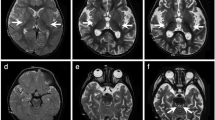

Patient 1, a 5-year-old boy, was born in a Chinese family with no family history of hereditary metabolic disease, with weighing 20 Kg, head circumference 52 cm and height 113 cm (Fig. 1A). He was G1P1 with a full-term normal delivery, and weighed 4000 g at birth. The patient frequently caught colds before the age of one and was admitted to the hospital at one and a half years old. Between the ages of 2 and 3 years, the patient’s feet were prone to peeling, and the symptom was relieved after vitamin B treatment. At 3 years and 10 months, the patient was readmitted with a high fever, weakness, and an inability to stand. The brain MRI diagnosed encephalitis. At 4 years, the patient’s brain MRI showed bilateral caudate nucleus and putamen nucleus were symmetrically swollen, and high diffusion weighted imaging (DWI) signal. (Fig. 1B) At 4 and a half years old, the patient experienced intermittent convulsions of both upper limbs, head, and face, and electroencephalography showed abnormal brain-wave activity. The patient’s brain MRI showed long T1 and T2 signals in the bilateral caudate nucleus and putamen nucleus, bilateral basal ganglia atrophy and brain sulci enlargement. Laboratory examination showed normal blood ammonia level (32 µM, normal range 18–60 µM). Whole exome sequencing (WES) and mitochondrial genomic sequencing were carried out to identify the disease-causing gene mutation. Following filtering with established criteria, two site variants (c.2090G > A and c.2122G > A) in the IARS2 gene were found, and no clinically significant mitochondrial genomic-related variants were observed. Segregation analysis confirmed that c.2090G > A from the patient’s mother and c.2122G > A from the patient’s father (Fig. 1C).

Family pedigree analysis, brain MRI images and variant analysis of IARS2. A. Pedigree analysis of patient 1 and patient 2 from two unrelated Chinese families. Rectangles indicated males, circles female, solid circle rectangled the affected individuals and probands were pointed out by arrows. B. Brain MRI images of patient 1 and 2. The patient 1 on the left showed lesions in the thalamus, periaqueductal, cerebellum and pons when he was 4 years old. The arrow pointed to the high signal were diseased areas. The patient 2 on the right showed long T1 and T2 signals in the lateral caudate nucleus and putamen, reduced cerebral white matter, bilateral basal ganglia symmetry damage, and cerebral dysplasia. The circled pointed to the symmetrical patchy were diseased areas. C. Sequencing chromatograms of IARS2 in patients and their parents. The arrows indicated the mutation sites. D. Quantitative analysis results of IARS2 in patient 2 and his parents

Patient 2, a 4-year-old boy, was born in a Chinese family with healthy parents (Fig. 1A). He was G3P3 with an abdominal delivery, and weighed 4350 g at birth. The child was admitted to the hospital at one and a half years old, weighing 13 kg, with a head circumference of 46 cm and a height of 73 cm. He couldn’t speak and had been diagnosed with growth retardation. It was hard for him to sit stably, and he was unable to walk or eat alone. The patient was readmitted at age 3 and diagnosed with dystonia and neurodevelopmental delays. Laboratory examination showed increased blood lactate (6.24 mM, normal range 0.50–2.20 mM), β-hydroxybutyric acid (1.05 mM, normal range 0.02–0.27 mM), and creatine kinase (1854.59 U/L, normal range 50–319 U/L). Brain magnetic resonance imaging (MRI) revealed long T1 and T2 signals in the lateral caudate nucleus and putamen, reduced cerebral white matter, bilateral basal ganglia symmetry damage, and cerebral dysplasia (Fig. 1B). He was subsequently diagnosed with LS. After filtering with established criteria, WES and mitochondrial genomic sequencing did not detect potential disease-causing gene mutations. Subsequently, whole genome sequencing (WGS) was performed. Following filtering with established criteria, a novel site variant (c.2450G > A) and a deletion variant with 1 and 2 exons (c.1_390del, NC_000001.11: g.220267444_220269568del) in the IARS2 gene were found, and no clinically significant mitochondrial genomic-related variants were observed. Segregation analysis confirmed that c.2450G > A was from the patient’s mother and c.1_390del was from the patient’s father (Fig. 1C). As shown in Fig. 1D, heterozygous mutations in IARS2 exon 1 and 2 of the patient were found by CNV-Seq. Quantitative PCR results showed that the mRNA level of IARS2 exon 1 and 2 in the patient and his father were significantly decreased compared with both age-matched controls and the patient’s mother.